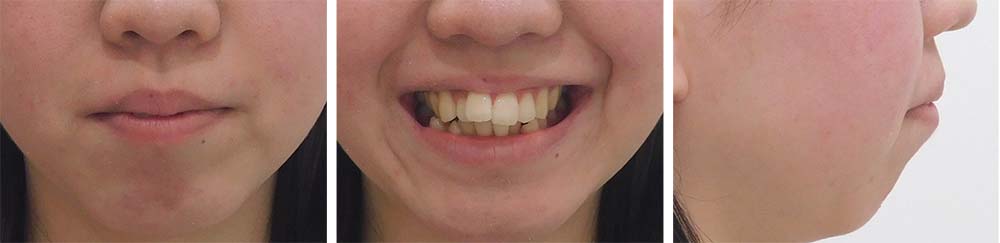

| 症例分類 | 叢生、上顎前突、口唇突出 |

| 診断名 | 下顎重度叢生を伴う骨格性上顎前突 |

| 主訴 | 歯並びが悪い、ものがよく噛めない、口元が気になる、歯科医師に勧められた |

| 年齢 | 22歳10ヶ月 |

| 性別 | 女性 |

下顎前歯重度叢生と上顎歯列の前方位、口唇閉鎖不全、口唇突出感があるため、上顎両側第一小臼歯と下顎両側第一小臼歯を抜去して治療を行いました。上顎前歯をしっかりと舌側移動しないといけなかったため矯正用アンカースクリューを使用しました。

前歯がしっかりと舌側移動できたため、口唇閉鎖不全が改善され口唇突出感もなくなり、問題なく咬合させることができました。